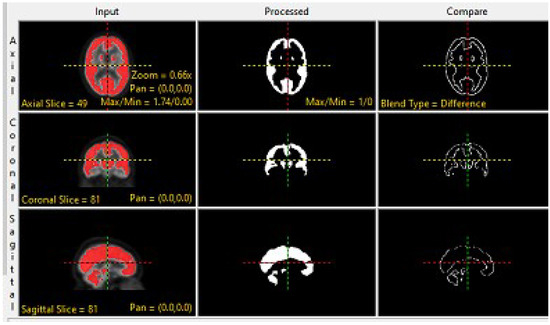

2.1. Preprocessing of MRI and PET Images

2.2. Proposed Fusion Technique of MRI and PET